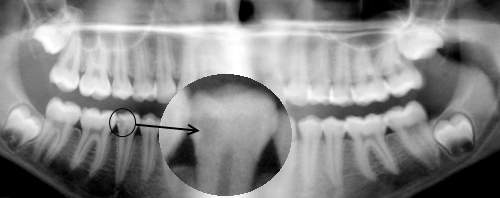

Radiographie panoramique:

La radiographie panoramique dentaire permet de visualiser sur un seul cliché: les arcades dentaires, les maxillaires, les sinus maxillaires.

Elle constitue un complément d'examen trés utile qui facilite le dépistage. Elle permet de visualiser, entre autre, la qualité osseuse, les dents incluses dans les maxillaires.

Détection d'une carie mésiale.